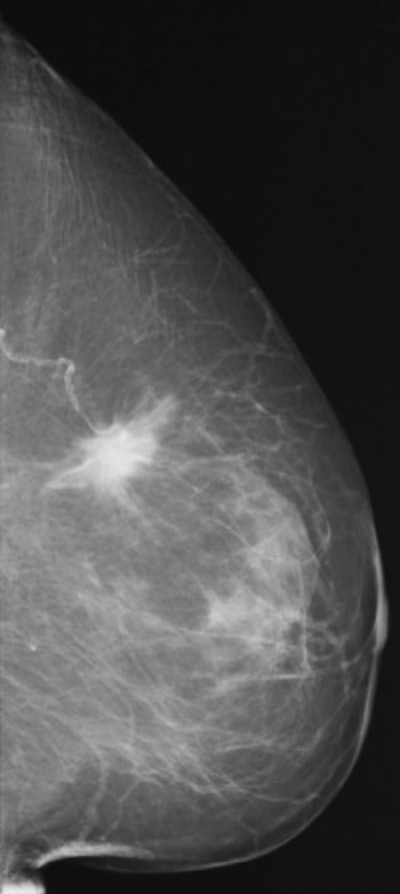

FFDM images acquired on the Senographe 2000D, including zoom (middle) and magnification (below). Images courtesy of Dr. Wolfgang Matzek.